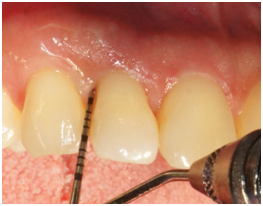

Supportive periodontal therapy was performed for the patient on a regular basis starting 6 weeks after surgery and every three months making sure not to instrument the surgical site subgingivally. The overall plaque control was optimal. The patient was recalled 6 months following surgery. Full-mouth periodontal charting was completed. The disto-palatal surface of tooth #7 exhibited a remarkable reduction in PD, BOP and mobility (Table 1). The patient was pleased with the esthetics and function at this time. A periapical radiograph obtained and demonstrated bone fill in the treated area with a uniform trabecular bone pattern (Figure 3) 12 months follow-up was performed that revealed consistent clinical findings when they were compared with those at 6 months. The disto-palatal surface of tooth #7 exhibited a remarkable reduction in PD to 4mm. There was a CAL gain of 5mm (Figure 4a & 4b). Tables 1 present probing measure at baseline, 6 and 12 months and documents a tendency for continued improvement in PD and CAL. The periapical radiograph at 12 months demonstrates a gain of interproximal bone height in the region between teeth #6 and #7 (Figure 5).

Figure 4a Probing 12 months after surgery reveals PD of 4 mm on the disto-palatal aspect of tooth #7.

Figure 4b Probing 12 months after surgery reveals PD of 3 mm on the disto-facial aspect of tooth #7.